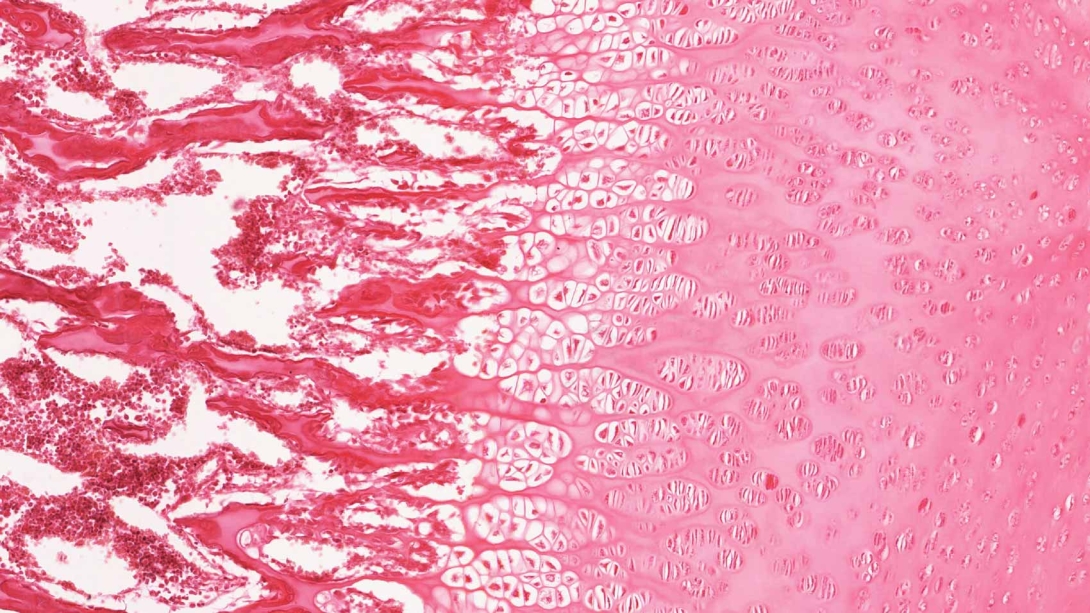

For all of them, nothing beats a microscope-level view of healthy organs, tissues and cells. That view sets the stage for learning how these structures change because of mutation, disease or the passage of time — and how to prevent, slow or stop those changes.

Now, students and teachers everywhere can see the human body in fine detail, thanks to "virtual microscopy," which has opened the body's secrets to a much wider audience of students and teachers.

In any given week, tens of thousands of people from more than 170 countries visit the site. With a few clicks, anyone can zoom in to view images at higher and higher magnification, ranging from an entire organ down to a single cell.

"Virtual microscopy is like Google Earth, just at the microscopic scale," he says. "It's not just about looking at pictures. It's also a way to connect structure with function. Because we are visual animals, it's easier for us to understand what is happening inside our bodies if we can see it with our own eyes."